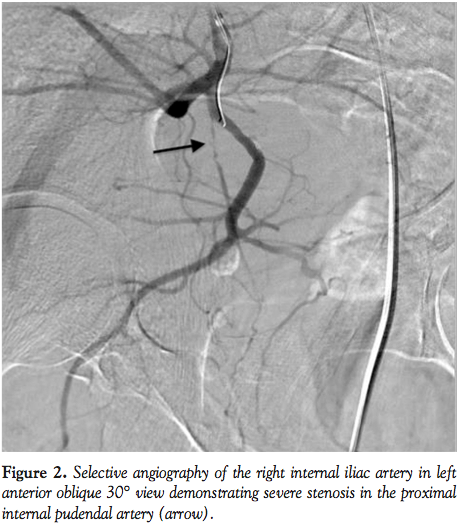

coated sheath that was advanced to the ostium of the right internal iliac artery over 0.035˝ wire. This wire was exchanged to 0.014˝, 300 cm coronary wire that was advanced into the right internal iliac artery. A 5 Fr angled Terumo Glide catheter was then advanced to the distal segment of the right internal iliac artery over the 0.014˝ wire. The sheath was then “telescoped” into the vessel and the Glide catheter removed. Angiography at 30°

right anterior oblique (RAO), 30° left anterior oblique (LAO), and AP projections was performed demonstrating a pudendal artery arising from the right internal gluteal artery with a severe lesion at the ostium of the pudendal artery and subtotal occlusion in the mid segment (Figure 2). There was slow flow in the vessel. The lesion was crossed with 0.014˝ coronary wire and dilated with a coronary 2.0 x 20 mm balloon inflated to 6 atm. There was an improvement in flow after angioplasty; however, there were areas of significant residual stenoses and a 2.5 x 24 mm drug-eluting coronary stent was deployed at 12 atm to optimize the result. This resulted in excellent angiographic result and normalization of flow in the vessel (Figures 3 and 4). There were no complications and the patient was discharged the same day. He reported significant improvement in erectile function at follow-up visit.